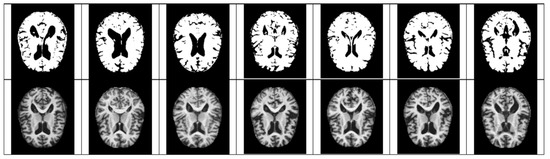

- For Z-score normalization, the interval to which each pixel belongs is converted to [−1, 1], and for min–max, it is converted to [0, 1]. During the computation of the convolutional neural network, the pixel intensity of [0, 255] is adjusted for fast convergence and accurate feature extraction.

- The size space of pixels constituting the Alzheimer’s MRI data set is [0, 255]. Among them, patients with AD with reduced hippocampus will have more pixels close to zero than normal people. On the premise of this, the average value of pixel intensities in each MRI image is set as a threshold value. Alzheimer’s should recognize changes in size contraction rather than changes in brain function. Based on this information, it is necessary to set the space as an important feature for the color information of MRI rather than a feature representing the shape of the brain.